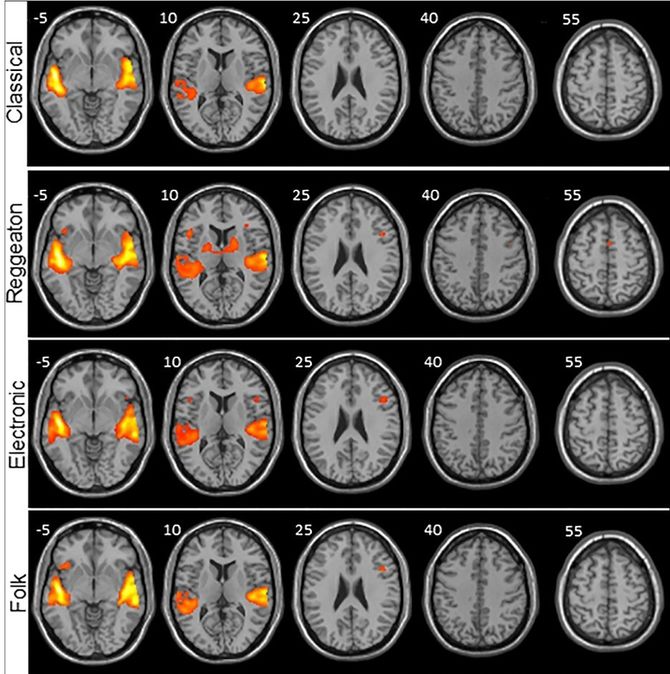

Después se sometió a las personas a una resonancia magnética funcional mientras escuchaban diferentes tipos y estilos de música sin letra, para estudiar de la manera más pura posible el procesamiento de la música. De no ser así, el lenguaje podría causar actividad cerebral, pero empleando otras vías que no son las de la música.

Los investigadores analizaron el cerebro de cada participante anatómicamente y después la señal Bold, que es la que muestra qué áreas del cerebro reciben oxígeno y qué es lo que pasa cuando se activan las diferentes áreas.

Tras poner música electrónica, clásica, folch y reguetón, el resultado fue increíble. El género urbano fue el estilo musical que activó más áreas del cerebro, tanto las auditivas, como las que procesan el sonido, las motoras y las de movimiento. Según explica Martín-Fernández

"Es como si el reguetón, con este ritmo peculiar y repetitivo, nos preparara para el movimiento, para bailar sólo de escucharlo", asegurando que este estilo musical utiliza los acuerdos de una manera predecible.

"Lo que más nos llamó la atención fue que activaba una región primitiva del cerebro: los ganglios basales", y añade que "Son grupos de neuronas que están en zonas profundas del cerebro y que se encargan de modular la postura, de empezar y terminar un movimiento además de estar involucrados en el sistema de recompensa o placer".